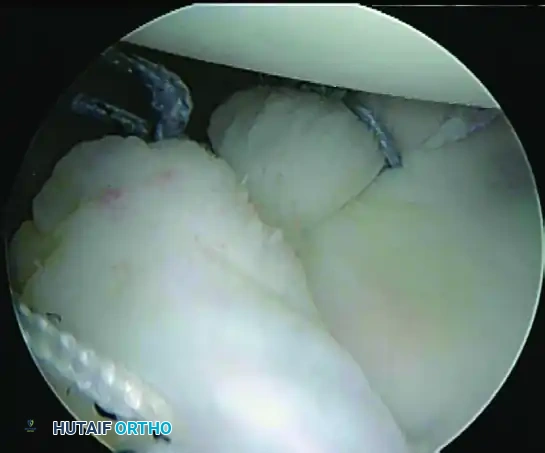

5. Recreating the Anterior Bumper

Proceed superiorly, placing the second and third double-loaded anchors. Firmly secure the sutures, compressing the capsuloligamentous complex to the abraded bone surface. This "loop and knot fixation" rolls the tissue up onto the glenoid face, recreating a robust anterior soft-tissue bumper.

D, Knots tied re-creating soft tissue bumper.

B, Restored anterior labral bumper (arthroscopic view).

C, Restored anterior labral bumper (alternate angle).

Final Construct Verification

Evaluate the final repair. The drive-through sign should be eliminated, the humeral head should be centered on the glenoid, and a prominent anterior bumper should be visible.